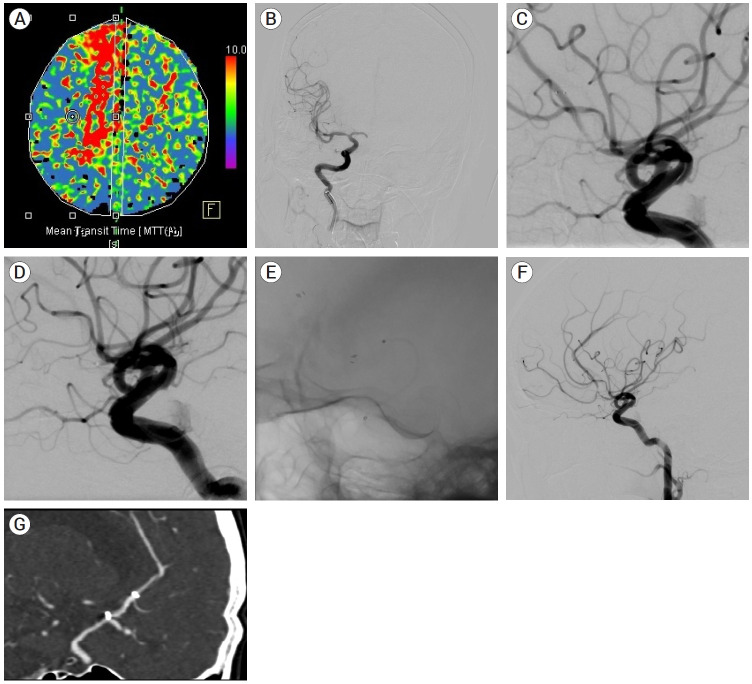

Objective: Treatment failure usually occurs within 24 hours after mechanical thrombectomy (MT) for acute intracranial atherosclerotic steno-occlusion (ICAS) and is an unexpected event that adversely influences the clinical outcome. We retrospectively evaluated the factors influencing reocclusion after MT plus rescue treatment in acute ICAS patients with successful recanalization.

Methods: From January 2013 to December 2020, 60 patients with ICAS who underwent MT plus rescue treatment with successful recanalization were included in our study. We classified the patients into a patency group (n=47, 78.3%) and a reocclusion group (n=13, 21.7%) based on CT angiography data obtained the day after MT plus rescue treatment.

Results: Intravenous tissue plasminogen activator (IV t-PA) in the patency group (n=18/47 (38.3%)) significantly differed from that in the reocclusion group (n=1/13 (7.7%)) (p=0.045). The number of thrombectomy attempts in the reocclusion group was significantly greater than that in the patency group (median [interquartile range], 2 [1-3] vs. 1 [0-1.5], p=0.004). According to the univariate logistic regression analysis, the only prognostic factor for reocclusion was the number of thrombectomy attempts (odds ratio (OR), 1.655 [1.046-2.619], p=0.032). Conclusions: In our study of ICAS patients who achieved successful recanalization after MT plus rescue treatment, the number of thrombectomy attempts was an independent prognostic factor for reocclusion after MT. Accordingly, for highly suspicious ICAS lesions, additional attempts at the MT should be carefully performed to prevent reocclusion.